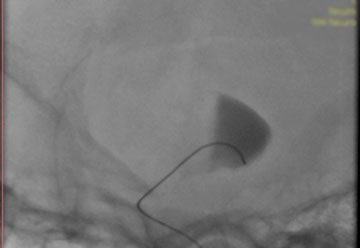

La paciente ingreso al Servicio de Hemodinamia el día martes 11 de febrero con un aneurisma cerebral gigante en la carótida izquierda y se le practicó una embolización; es decir una oclusión por dentro del mismo, donde se colocó un dispositivo denominado coils más un stent diversor de flujo. El procedimiento fue exitoso y contó con la colaboración de médicos neurointervencionistas del Instituto Oulton de la Ciudad de Córdoba.